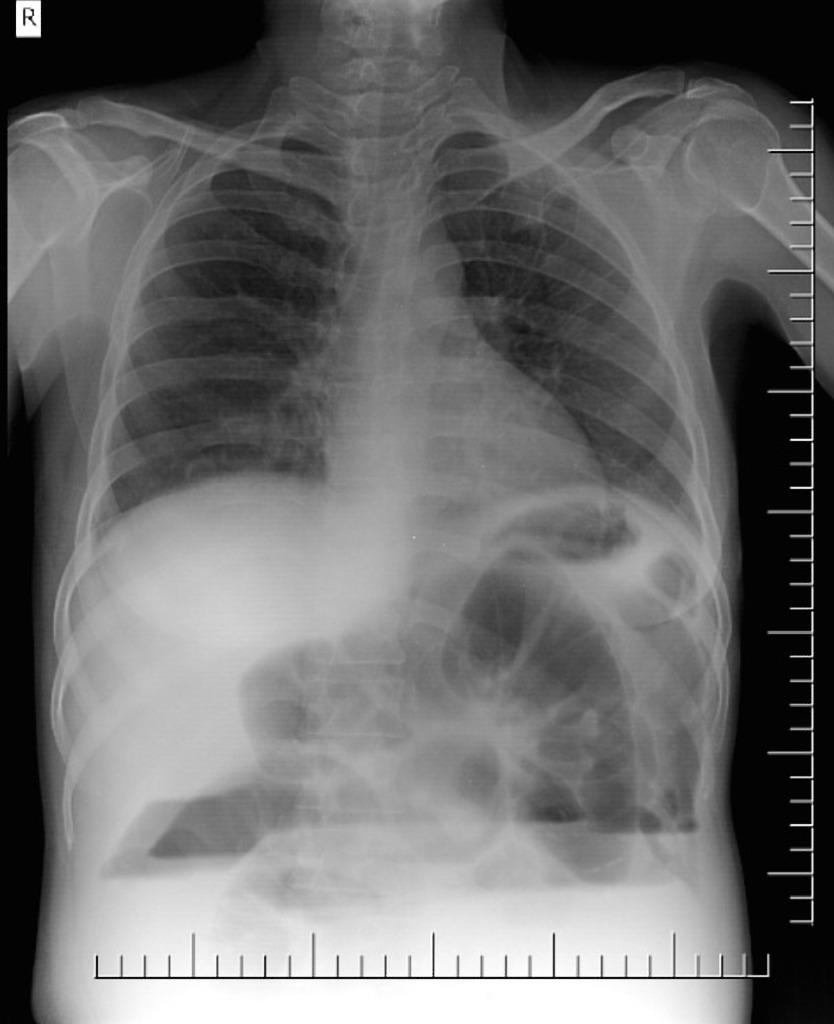

From www.shutterstock.com

Chest Xray Feature Intestinal Obstruction Child Stockfoto 788225221 Small Bowel Obstruction Chest Pain The pain from a small bowel obstruction is more likely to come in short. Treated by many different types of medical providers, including. Small bowel obstruction (sbo) is a very common problem for patients; Early signs and symptoms of a partial or complete intestinal obstruction include abdominal pain or distention, fever, rapid heart rate, and the inability. Small bowel obstruction. Small Bowel Obstruction Chest Pain.